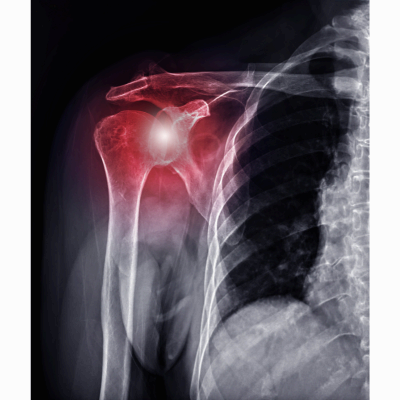

어깨 충돌 증후군

어깨 관절의 모양을 보면 뼈가 움직이기 위한 공간을 볼 수 있습니다.

이 공간 사이로 힘줄과 인대, 신경 등 다양한 기관이 지나가는데,

어깨가 움직이면서 이 부분들이 압박을 받거나 부딪히면서 통증을 일으킬 때 우리는 충돌증후군이라고 부릅니다.